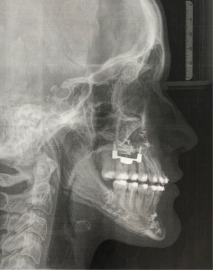

Nachher

Therapie:

Surgery First: Bignathe Umstellungsosteotomie (Minimalinvasive Le Fort I Osteotomie mit Vorverlagerung und simultaner Oberkieferdistraktion, gesonderte Spina Nasalis Osteotomie zur besseren Kontrolle von Oberlippenposition und -volumen, Anhebung der Nasenspitze, Unterkiefersegmentosteotomie 32-42 zur Vergrößerung der sagittalen Stufe (Dekompensation),

Kinnosteotomie, Side Wing Osteotomie mit Beckenkamminterponat)